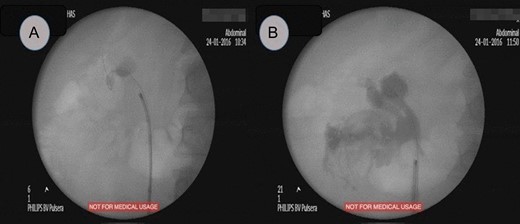

This is a 45-year-old female patient known to have diabetes mellitus and old cerebrovascular attack presented with right flank pain. Laboratory investigations revealed normal WBC count with a hemoglobin 10.4 mg/l. Radiological investigation showed right a 20 mm right renal stone (Fig. 1). Patient underwent FURS-L using a 10/12Fr Ureteral Access sheath. We did endoscopic renal exploration plus laser lithotripsy using Flex-Xc STORZ. The irrigation was under hydrostatic pressure of 80 cm H2O. The procedure was uneventful with an operative duration of 88 minutes. However, severe extravasation was noted at the end (Fig. 2). Six hours postoperatively the patient started to have high grade fever with a sudden drop of hemoglobin level to 6.6 mg/l. Immediate abdominopelvic CT scan with contrast was carried out showing severe right subcapsular renal hematoma. This complication was managed conservatively through proper antibiotics, blood transfusion and good hydration for 7 days. The patient was seen in the outpatient clinic 2 months later with a new abdominopelvic CT scan which showed a regression of subcapsular renal hematoma and surprisingly migration of stone fragments into the regressed subcapsular hematoma (Fig. 3). On the other hand, the upper urinary tract was free of stones.

Fluoroscopic study, (A) showed a radiopaque shadow at level of L2, (B) showed extravasation of contrast at the end of surgery.